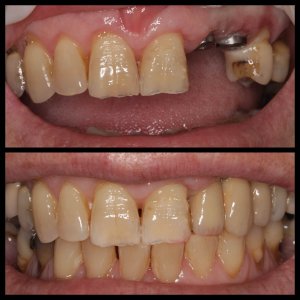

ΠΡΟΣΘΕΤΙΚΕΣ ΑΠΟΚΑΤΑΣΤΑΣΕΙΣ ΜΕ ΣΥΝΔΥΑΣΜΟ ΛΕΥΚΑΝΣΗΣ, ΣΥΝΘΕΤΩΝ ΡΗΤΙΝΩΝ ΚΑΙ ΟΛΟΚΕΡΑΜΙΚΩΝ ΟΨΕΩΝ ΚΑΙ ΣΤΕΦΑΝΩΝ

ΠΕΡΙΣΤΑΤΙΚΑ ΜΕ ΤΟΠΟΘΕΤΗΣΗ ΕΝΔΟΟΣΤΙΚΩΝ ΕΜΦΥΤΕΥΜΑΤΩΝ. ΌΠΟΥ ΧΡΕΙΑΣΤΗΚΕ ΠΡΑΓΜΑΤΟΠΟΙΗΘΗΚΕ ΑΝΑΠΛΑΣΗ ΟΣΤΟΥ ΚΑΙ ΟΥΛΙΚΩΝ ΕΛΕΙΜΜΑΤΩΝ ΜΕ ΧΡΗΣΗ ΜΟΣΧΕΥΜΑΤΩΝ ΚΑΙ PRF